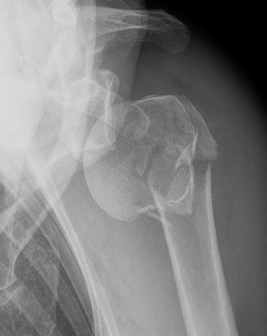

Holstein Lewis fracture

Holstein-Lewis JBJS Am 1963

- series of 7 oblique distal third fractures with radial nerve injury

- all were treated operatively

- nerve in fracture gap in 2 / impaled in 1 / severed in 2 / contused +/- in callus in 2

- advised against attempted closed reduction

- risk of contusing nerve between fragments

- advised early open reduction through anterolateral approach

- the radial nerve is closely assoicated with the fracture site and the fracture spike